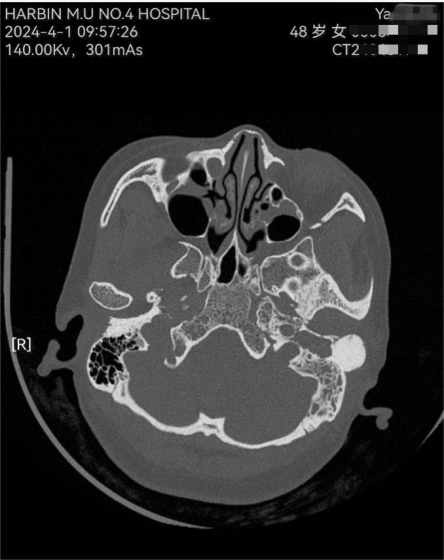

影像学干货|颞骨ct解剖(轴位)

哈医大四院耳鼻咽喉头颈外科成功救治一例颞骨骨瘤伴耳部并发症患者